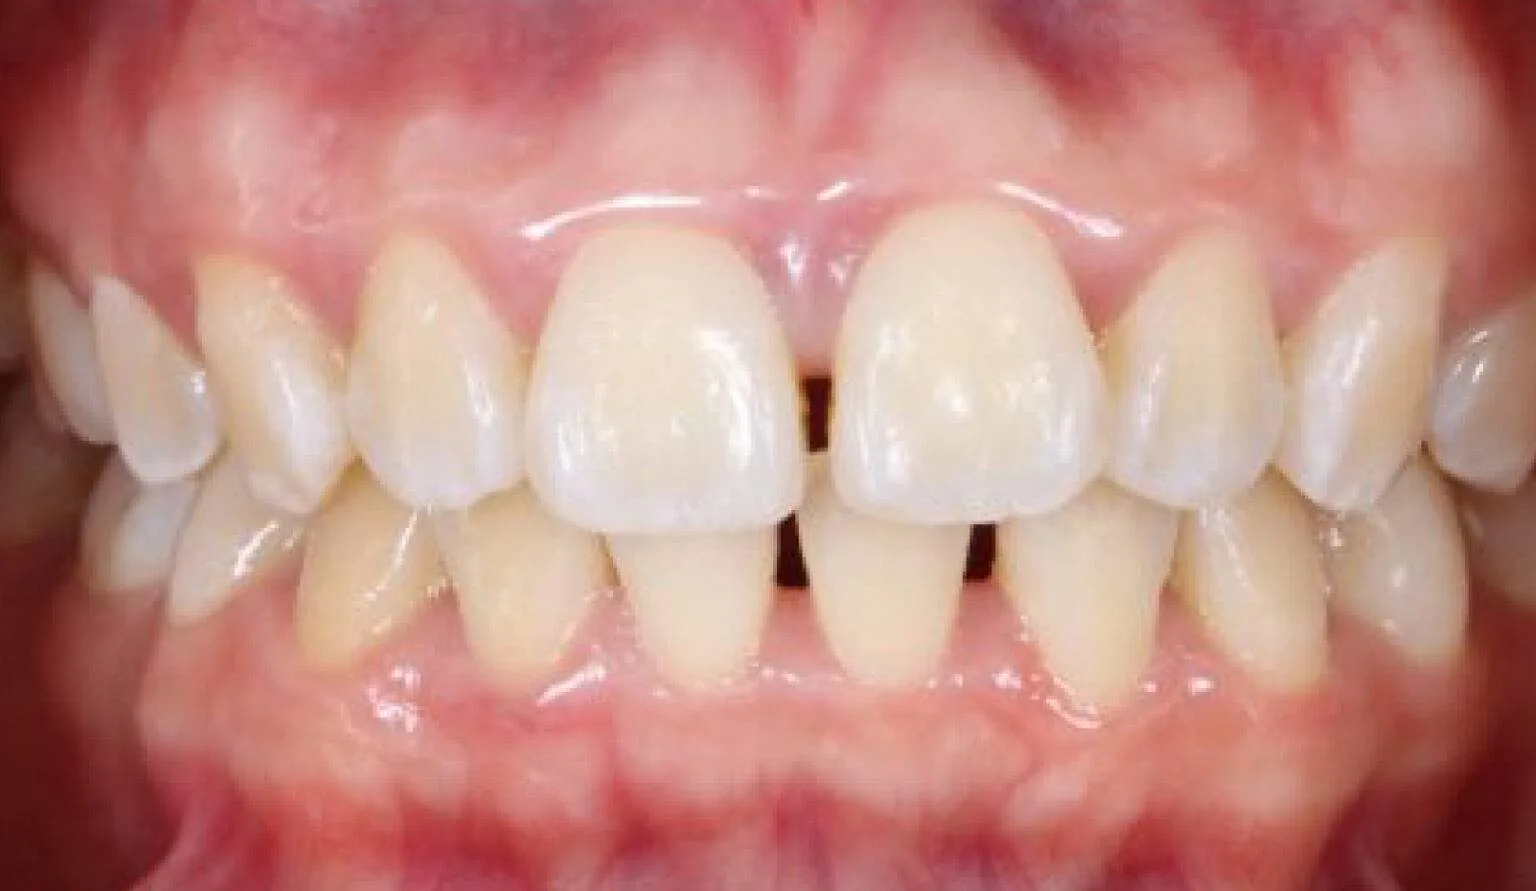

Before open bite treatment showing misaligned front teeth at SmileBox Dental Clinic After open bite treatment showing improved alignment and bite at SmileBox Dental Clinic